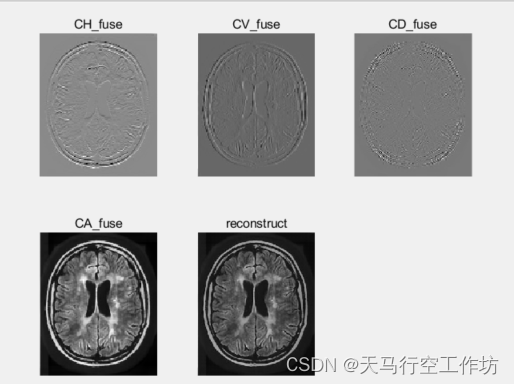

一层小波分解,低频采用邻域加权方差融合,高频采用基于局部梯度信息的融合算法

%第一层小波融合高频,邻域方差加权平均

CH_fuse=fuse_variance(CH,ch);

CV_fuse=fuse_variance(CV,cv);

CD_fuse=fuse_variance(CD,cd);

%第一层小波融合低频,局部梯度信息

CA_fuse=diff_local(CA,ca);

%逆变换恢复

result_fuse_1=idwt2(CA_fuse,CH_fuse,CV_fuse,CD_fuse,'haar');%一层小波分解二维图像信号

subplot(2,3,1),imshow(CH_fuse,[]),title('CH\_fuse');

subplot(2,3,2),imshow(CV_fuse,[]),title('CV\_fuse');

subplot(2,3,3),imshow(CD_fuse,[]),title('CD\_fuse');

subplot(2,3,4),imshow(CA_fuse,[]),title('CA\_fuse');

subplot(2,3,5),imshow(result_fuse_1,[]),title('reconstruct');